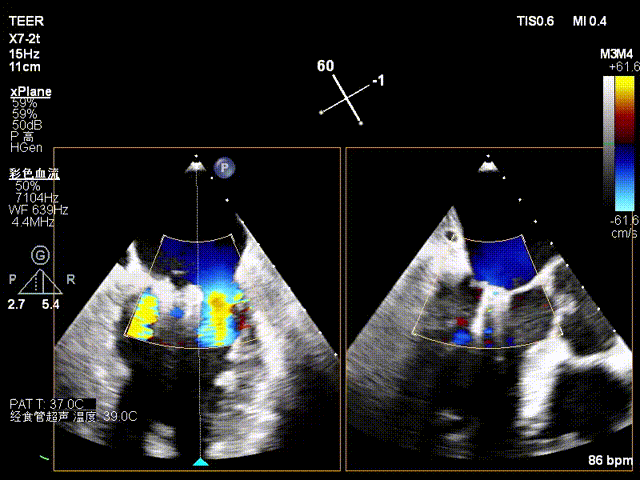

术前潘宏伟教授、何晋教授团队讨论决定,先于2偏1区置入一枚长宽(XW0612)夹解决最大的一处脱垂,再依次向内侧补夹子。术中房间隔穿刺高度:4.4cm,于2偏1区植入一枚长宽(XW0612)夹,夹闭后L侧无残余脱垂。再于M侧2区Side by side植入一枚长宽(XW0612)夹,夹闭后第一枚夹子较前稳定,M侧有残余脱垂。最后于M侧2偏3区植入一枚长窄(XN0412)夹,夹闭后残余功能性反流Trace,压差5mmHg,术毕,反流即刻由术前重度降低为Trace,左房压由术前45mmHg降至术后22mmHg,肺静脉逆流几乎消失,患者明显获益。

术前影像

X-plane 2区

X-plane 2区彩色

TMPG:5mmHg

术前静脉逆流

术后静脉逆流